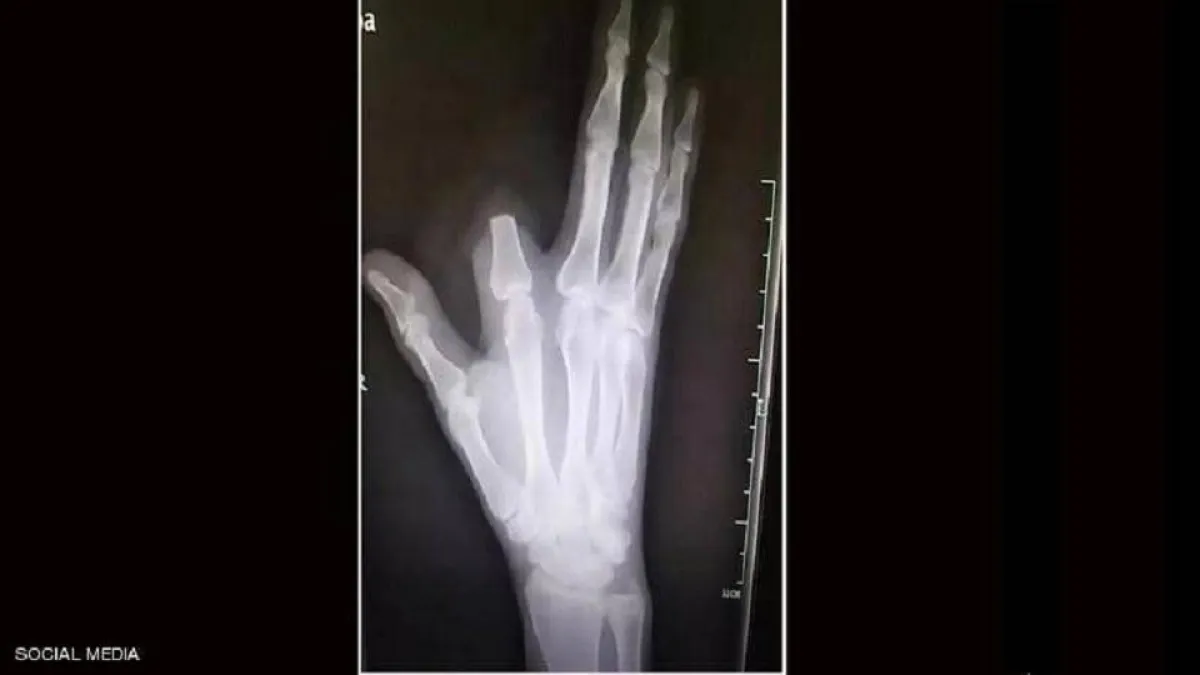

وظنّ الرجل أنّ لدغة الأفعى شديدة السميّة وقد تؤدي إلى موته ، فسارع إلى قطع إصبعه بسكين كان بحوزته من أجل "إنقاذ حياته"، بحسب ما أوردت شبكة "فوكس نيوز".

لكنّ الرجل الذي اتخذ القرار المؤلم بقطع إصبعه، لم يكن مضطرًا لفعل ذلك، لأنّ سمّ هذا النوع من الأفاعي ليس قاتلًا ، بل إنه يُستخدم في تحضير علاجات للمفاصل والعظام.